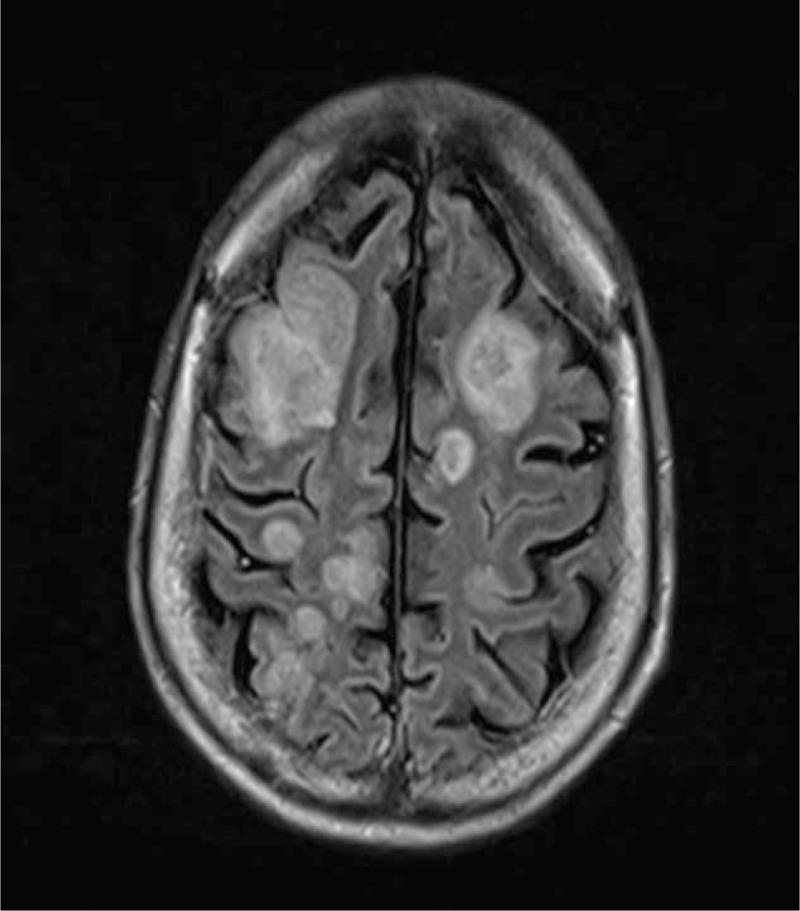

Invasive cerebral aspergillosis always developed in immunocompromised host. Early diagnosis may save life in this critical condition; however, it is difficult to reach. Herein, we presented an unusual case of invasive cerebral aspergillosis in a cirrhotic patient. A 47-year-old man presented with progressive deterioration of consciousness for three days. The patient had a history of alcoholic liver cirrhosis, Child-Pugh class C. Magnetic resonance imaging (MRI) of brain showed multi-focal parenchymal lesions, which was consistent with multiple brain abscesses. The diagnosis of invasive cerebral aspergillosis was made by molecular based laboratory methods including Aspergillus galactomannan antigen assay and oligonucleotide array. Despite treatment with the antifungal agent, Amphotericin B, the patient died at the ninth day of hospitalization. Our findings suggest that liver cirrhosis can be one of risk factors of invasive cerebral aspergillosis, and support the diagnosing usefulness of MRI, Aspergillus galactomannan antigen assay, and oligonucleotide array.